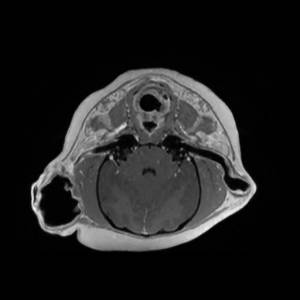

Main Gallery

Playing with a photo gallery function. It is possible to have multiple galleries, each within a namespace.